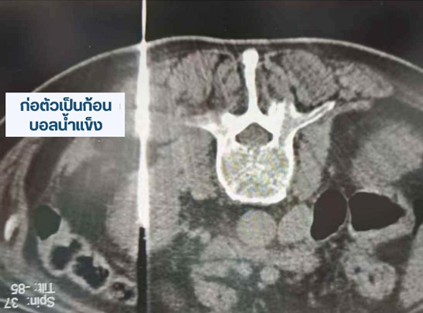

คุณหลี่ (นามสมมติ) อายุเกือบ 80 ปี อาศัยอยู่ในเขตมองโกเลียใน เมื่อเดือนกันยายนที่ผ่านมา เขาเริ่มมีอาการปวดบริเวณไตขวา จึงเข้ารับการตรวจที่โรงพยาบาลท้องถิ่น ผลการตรวจสร้างความกังวลอย่างมาก พบภาวะไตขวาบวมน้ำ (Hydronephrosis) ไตซ้ายฝ่อลีบ และตรวจพบก้อนขนาดประมาณ 3.9 เซนติเมตรที่ไตซ้าย

การจี้เย็น (Cryoablation) เป็นการทำลายเซลล์มะเร็งด้วยการแช่แข็งที่อุณหภูมิต่ำมาก ส่งผลให้เซลล์มะเร็งตาย วิธีนี้ก่อให้เกิดการบาดเจ็บต่อร่างกายน้อย ฟื้นตัวได้รวดเร็ว จึงเหมาะอย่างยิ่งสำหรับผู้ป่วยสูงอายุที่มีโรคประจำตัวหลายอย่าง